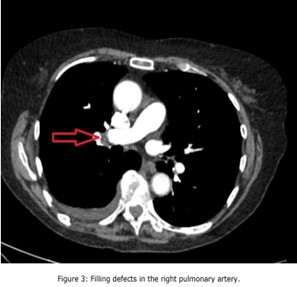

Given the persistent patient's symptoms despite completing the course of oral antibiotics, and raising D-dimer, a CTPA was performed to rule out PE which demonstrated multiple filling defects in the right lower pulmonary artery and its segmental with subsegmental branches, and patchy consolidations in the right lower lobe with mild right pleural effusion suggestive of infective/inflammatory aetiology ( Figure 3, Figure 4, Figure 5, Figure 6 and Figure 7).

Figure 3: Filling defects in the right pulmonary artery.